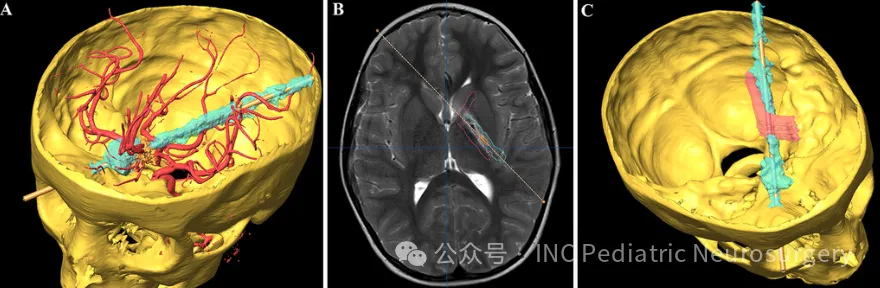

下图1:患者头骨及损伤轨迹三维重建

下图2A:异物经右侧眼眶进入颅骨的轨迹

下图2B:异物与脑实质内功能结构的解剖关系